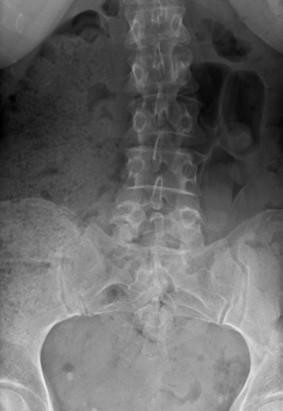

This patient was sent for plain film X-ray of the lumbopelvic spine.

Imaging indicated anomalies at the lumbosacral junction including a tropism at L5/S1 region. The right joints were more sagittaly oriented and the left joints were more coronally oriented. This patient also has a lateral rotary curvature concavity to the right with a pelvic lateral tilt. It is undetermined at this time if this patient’s curvature is secondary to muscle spasms associated with this injury.